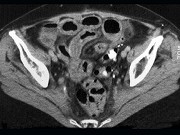

女,54岁,直肠癌放疗后1月,阵发性腹痛腹胀,呕吐应,CT表现如图,应诊断为()

女,54岁,直肠癌放疗后一月,阵发性腹痛腹胀,呕吐应,CT表现如图,应诊断为()<img border="0" style="width: 155px; heigh

[单选题]女,54岁,直肠癌放疗后一月,阵发性腹痛腹胀,呕吐应,CT表现如图,应诊断为()A.小肠淋巴瘤B.小肠结核C.小肠Crohn病D.放射性小肠炎E.肠易

女,54岁,直肠癌放疗后1月,阵发性腹痛腹胀,呕吐应,CT表现如图,应诊断为()

[单选题]女,54岁,直肠癌放疗后1月,阵发性腹痛腹胀,呕吐应,CT表现如图,应诊断为()A .小肠淋巴瘤B .小肠结核C .小肠Crohn病D .放射性小肠炎E .肠易激综合征

女,54岁,直肠癌放疗后1月,阵发性腹痛腹胀,呕吐,CT表现如图,应诊断为

[单选题]女,54岁,直肠癌放疗后1月,阵发性腹痛腹胀,呕吐,CT表现如图,应诊断为A . 小肠淋巴瘤B . 小肠结核C . 小肠Crohn病D . 放射性小肠炎E . 肠易激综合征

女,54岁,直肠癌放疗后1月,阵发性腹痛腹胀,呕吐,CT表现如图,最可能的诊断为

[单选题]女,54岁,直肠癌放疗后1月,阵发性腹痛腹胀,呕吐,CT表现如图,最可能的诊断为()A .小肠淋巴瘤B .小肠结核C .小肠Crohn病D .放射性小肠炎E .肠易激综合征